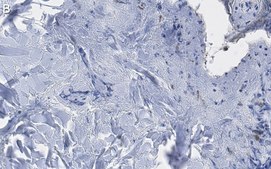

免疫组织化学(石蜡)分析:一个代表性批次的1:100稀释液在人皮肤组织切片中检测到III型胶原蛋白。